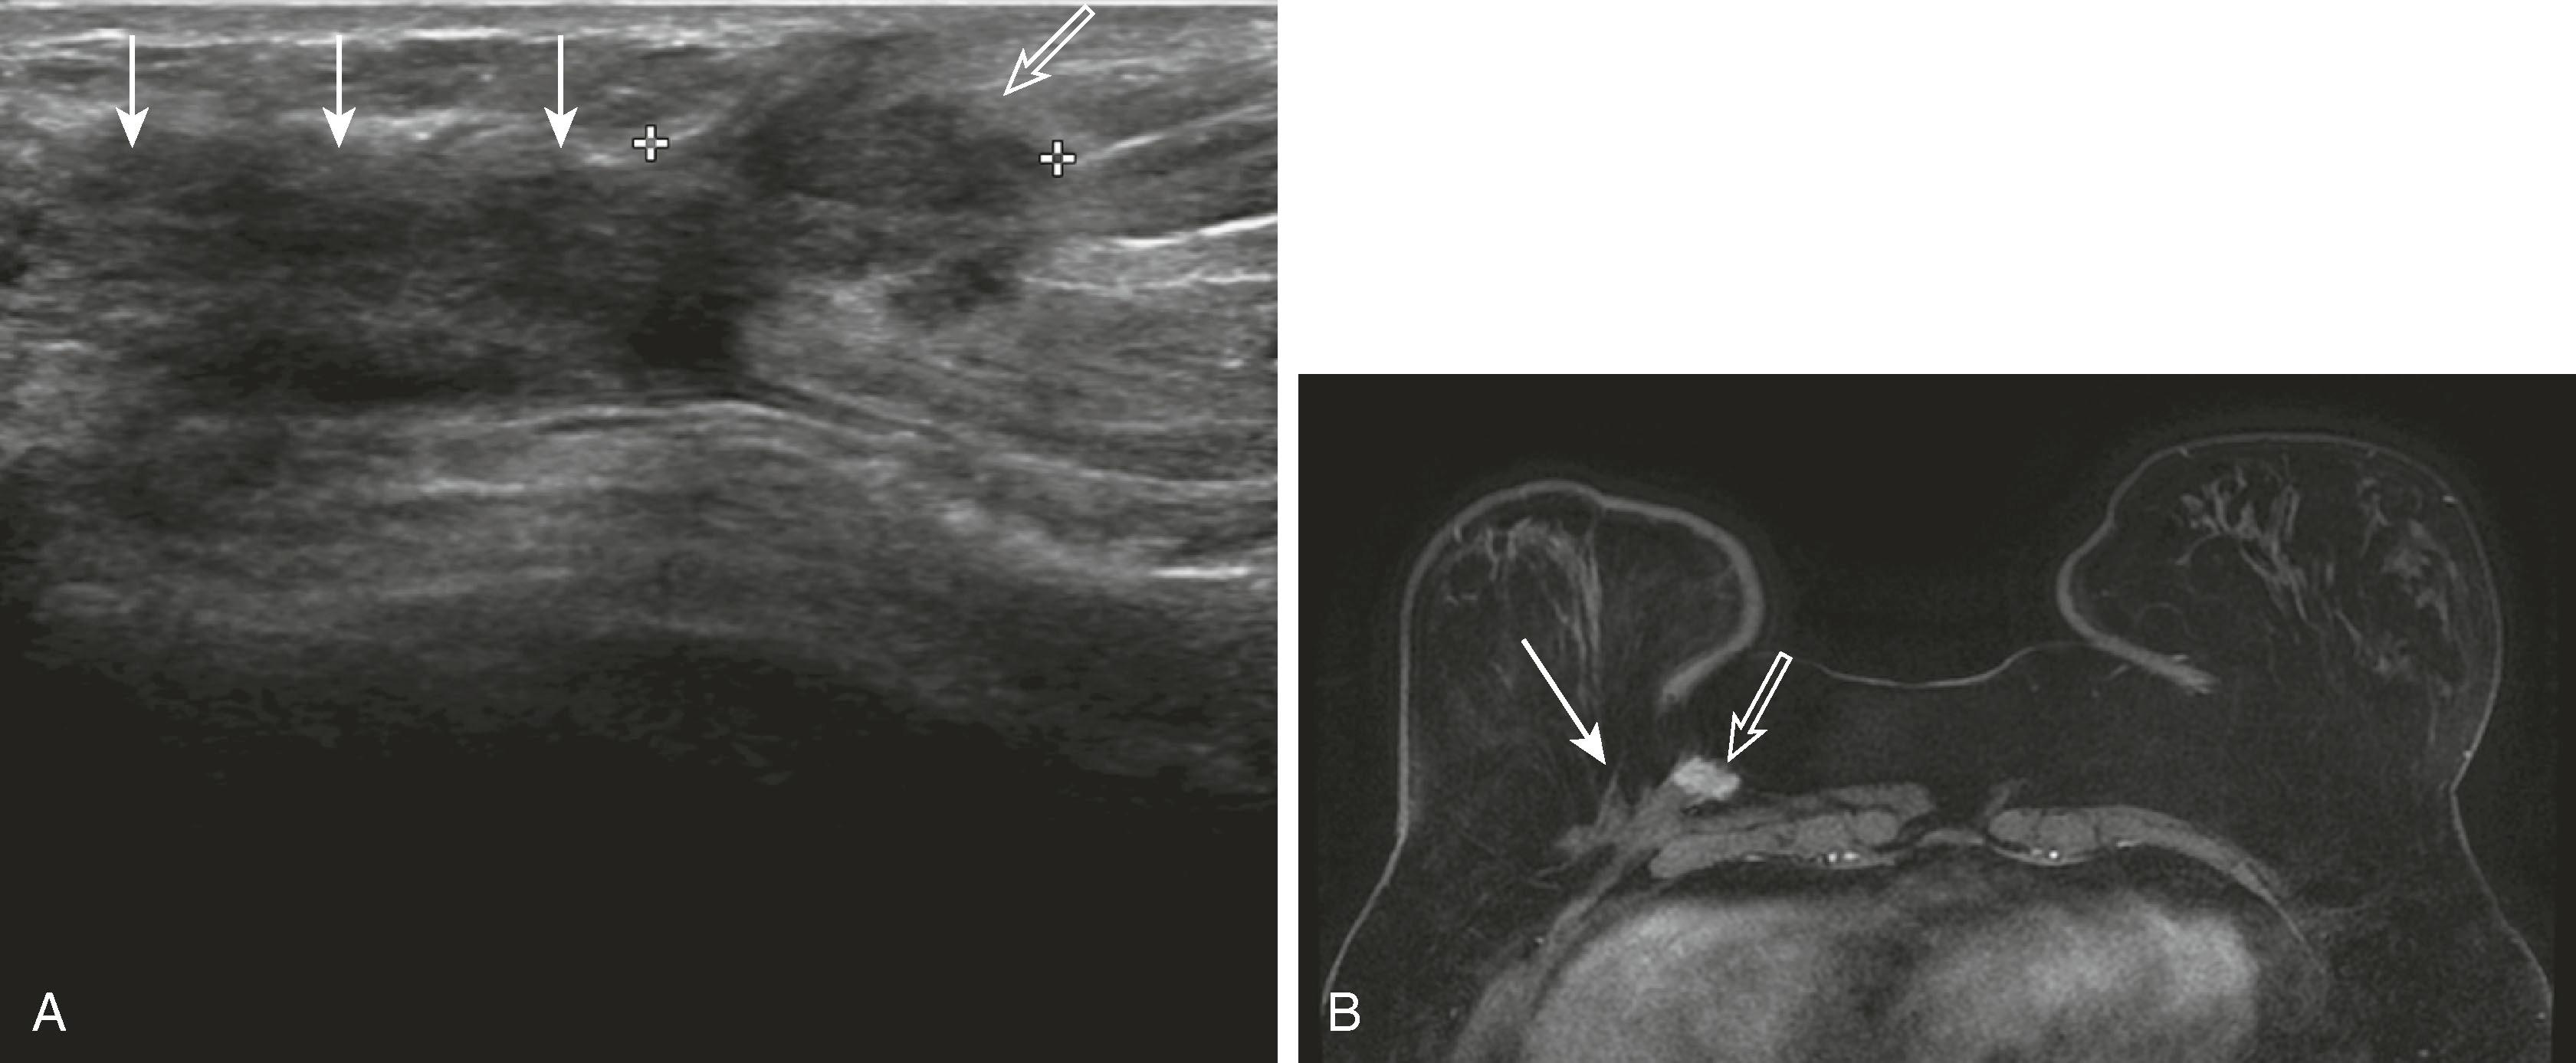

If a mass has suspicious features on mammography, ultrasound will be performed to further characterize it, to guide percutaneous needle biopsy, and to assess for additional disease in the breast and axilla. Sonographic features associated with invasive carcinoma are irregular shape, marked hypoechogenicity, ill-defined or angular margins, anteroposterior diameter greater than transverse diameter (taller than wide), and acoustic shadowing (greater attenuation of sound by the lesion compared with surrounding tissue, allowing less sound to pass through it) ( Fig. 8.18 ). The appearance of a surgical scar can mimic malignancy, so careful correlation with the mammogram, physical examination, and history is essential ( Fig. 8.19 ).

Fig. 8.18, Features commonly seen with infiltrating carcinomas. ( A ) A 9-mm invasive ductal carcinoma (IDC) with irregular shape and angular margins. ( B ) Palpable IDC with ill-defined margins. ( C ) Infiltrating lobular carcinoma with acoustic shadowing (arrows) . ( D ) A 1.4-cm IDC is taller in the vertical direction than it is wide in the horizontal orientation.

Fig. 8.19, ( A ) A surgical scar is often hypoechoic (solid arrows) and difficult to distinguish from a mass (open arrow) , requiring correlation with the location of the lumpectomy site on mammography and physical examination. ( B ) The hypoechoic mass merging with the scar was identified by its enhancement on magnetic resonance imaging (open arrow) , seen medial to the scar (solid arrow) . Ultrasound-guided core biopsy revealed recurrent invasive ductal carcinoma.